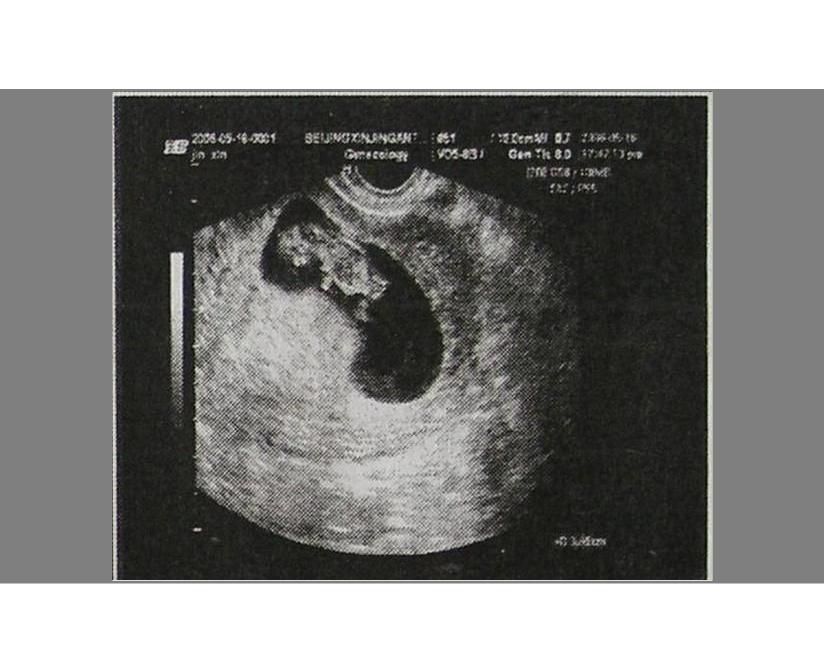

孕妈不放心的话,可以通过B超在宫腔内看到孕囊,随着胚胎不断成长,孕囊内会形成胎芽、胎心,如果孕妈在医院检查时,看得到孕囊,胎心和胎芽,就可以确认为宫内妊娠。

- 30到40天形成胎囊;

- 40到50天形成胎芽;

- 50-60天形成胎心;

医院会建议孕妇在怀孕42天时去所在地的妇产医院建档,做B超检查,这时候一般会看到完整的孕囊,如果月经不是很规律,可以晚一点去。

一般在42天左右去医院做个B超检查,可以看到完整的孕囊 。